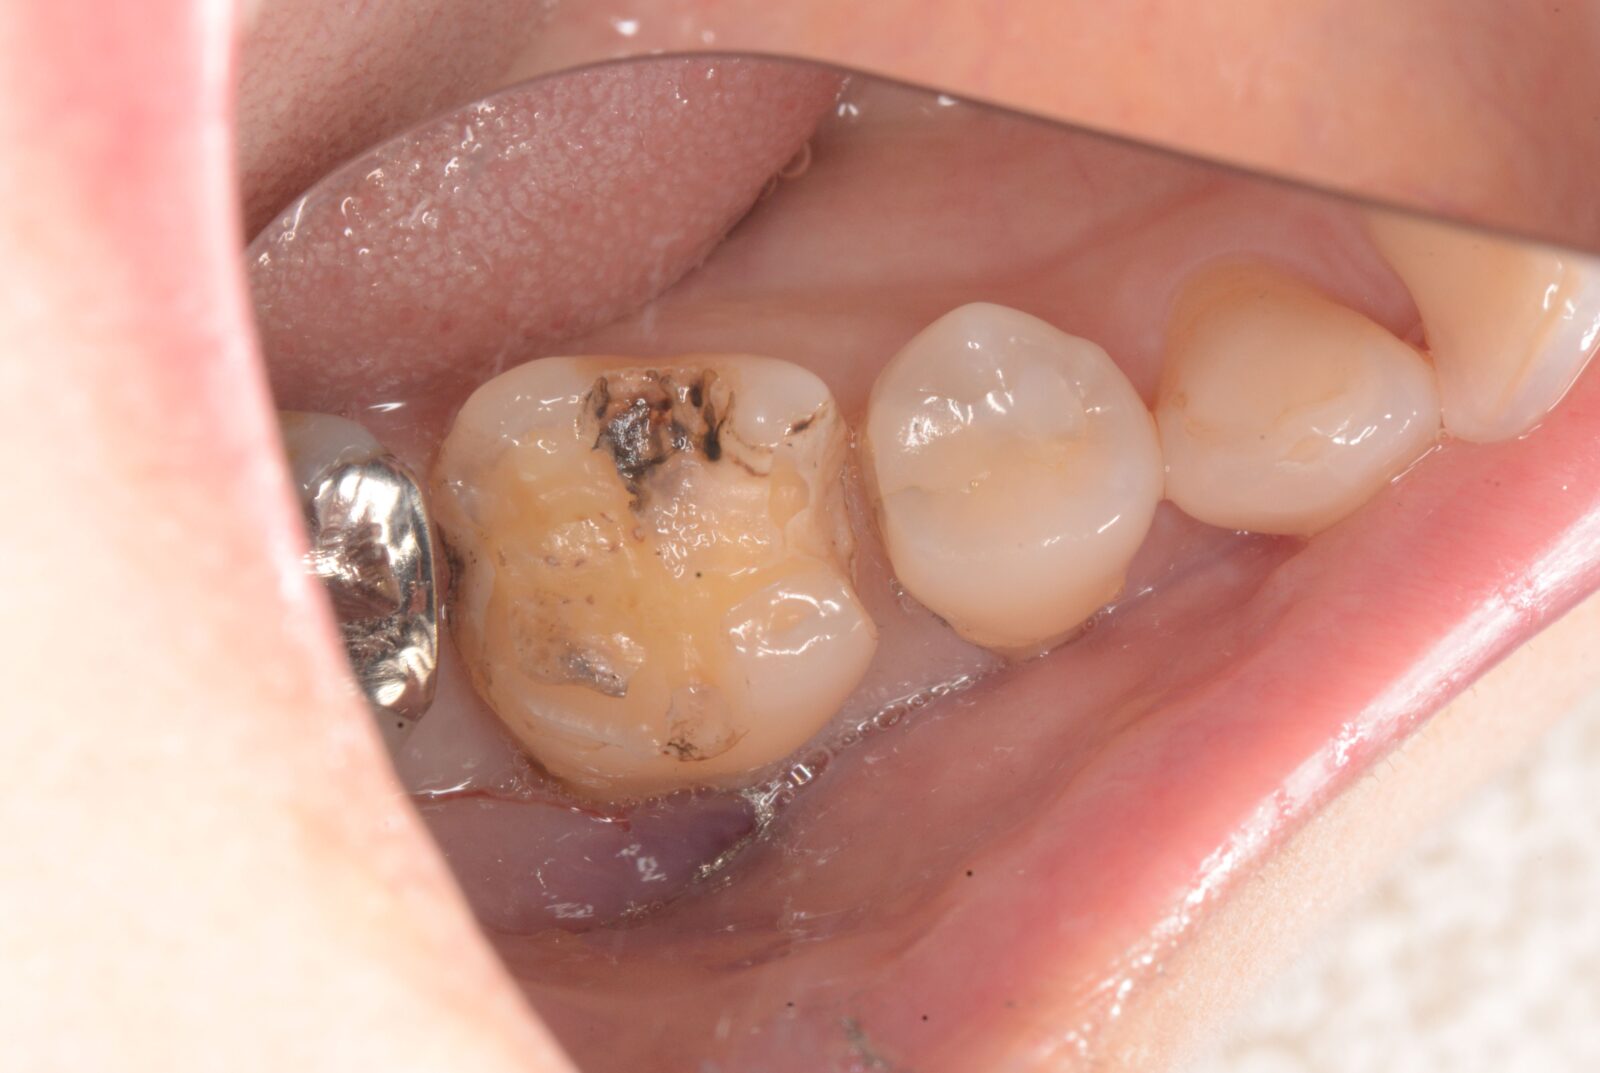

右上7精密根管治療~セラミックス補綴

噛んだ時の違和感を訴えられ、以前のセラミックスクラウンを除去し根管治療開始。 ラバーダム下での2回の根管治療を経て、根管充填と支台築造を行った状態から、精密なクラウン用の形成と印象を行い、セラミックスクラウンの装着。 奥から2番目の他院のセラミックスは縁取りが歯と合っておらず、また、表面…